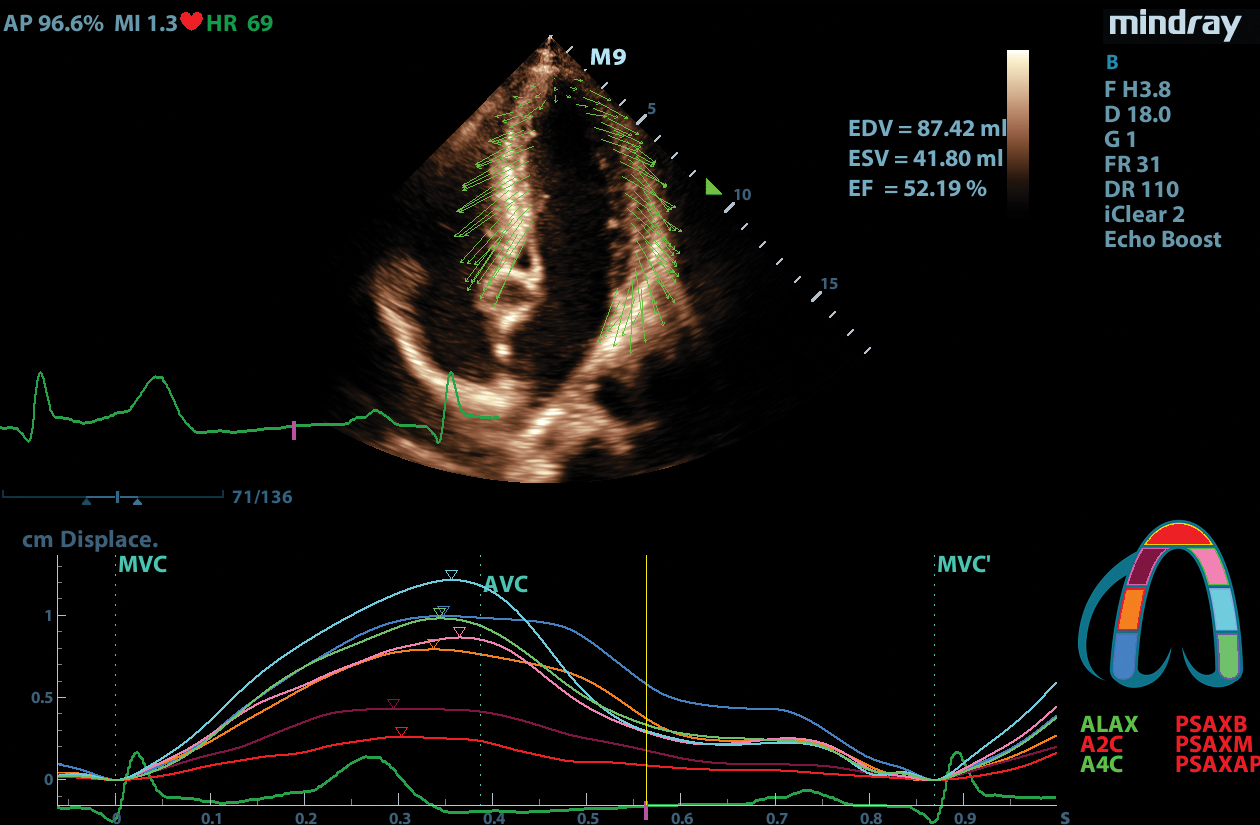

Tissue Tracking

Mindray’s Tissue Tracking technology with quantitative analysis allows users to monitor the displacement of cardiac tissue by tracking the speckle displacement in the image from frame to frame. This non-angle dependent tool with onboard analysis, can be performed at the bedside, saving time and simplifying challenging cases.